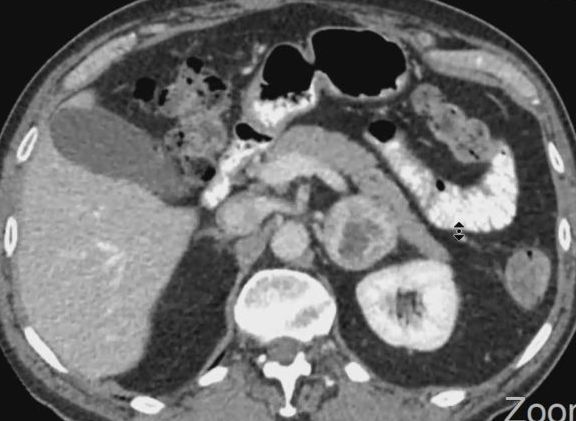

CT mit KM | |

| zurück Home | Phaeochromozytom | Phäochromozytom der linken Nebenniere

| Klinik | Tumor des Nebennierenmarks. Sezernieren Katecholamine. | ||

| Lokalisation | 98% im Abdomen. 10% doppelseitig. | ||

| extraadrenal | 10% der Phaeochromozytome sind extraadrenal und heißen Paragangliome. | Es ist wichtig, festzustellen, ob der Tumor in der Nebenniere oder daneben liegt. Intraadrenale Tumoren sind immer benigne, paraadrenale zu 20% maligne. | |